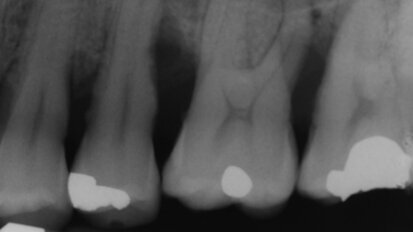

Terapia parodontale non chirurgica con approccio “One-Stage Full-Mouth Disinfection”

Le malattie parodontali possono causare gravi invalidità quali la perdita o la riduzione della funzionalità dell’apparato ...